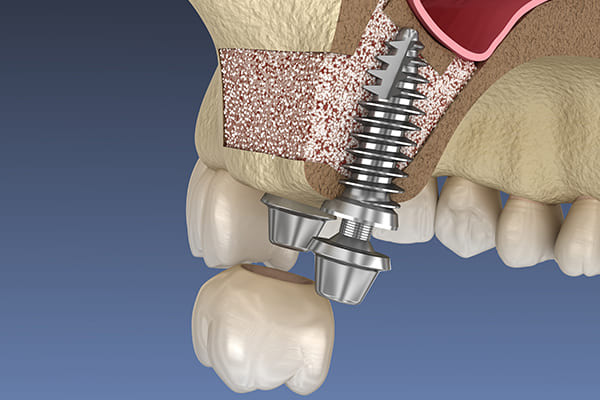

サイナスリフト

上顎には上顎洞と呼ばれる空洞があります。

この上顎洞から歯の部分までの骨の高さが不足している場合に、人工骨や自身の骨を移植することにより、上顎洞にインプラント埋入に必要な骨の厚みを作り出す方法です。